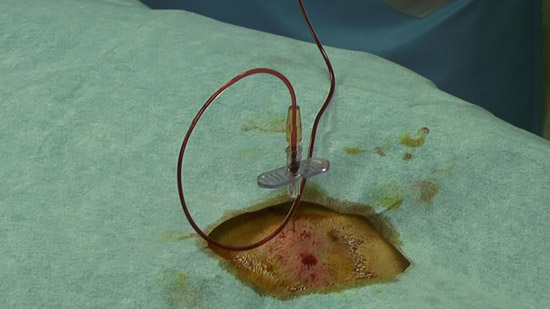

(6) Join an extension tube

Conduct the procedure with the extension tube hereafter

(7) Measurement of the lumbar puncture pressure

Measure the pressure with a glass rod placed in parallel to the extension tube

(8)Omnipaque 10 mL infusion

(9)Successively, inject indium 1 mL

Inject indium steadily using air pressure